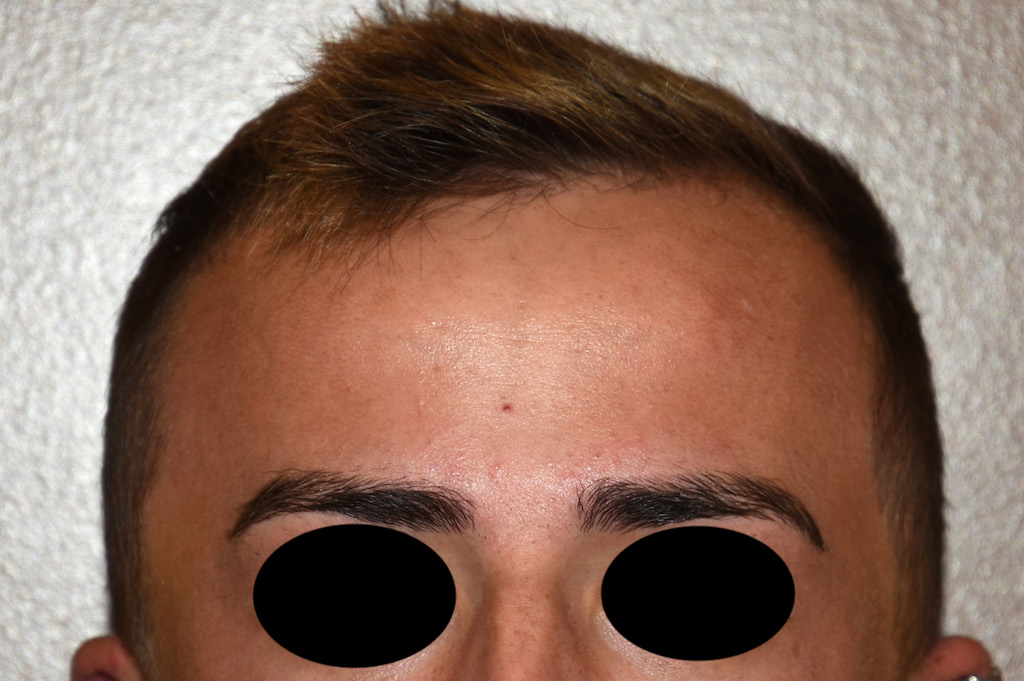

Desire for a higher and more prominent crown of the skull.

Crown of skull augmentation using a custom skull implant.

Desire for a higher and more prominent crown of the skull.

Crown of skull augmentation using a custom skull implant.